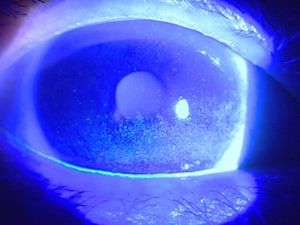

結膜炎・白内障・緑内障・ドライアイ・眼精疲労(目の疲れ)・かすみなどをはじめ、各種検査・コンタクトレンズ・めがね処方も行っております。小児や赤ちゃんの目の不調なども診療しております。当院では、最新の検査機器、治療機器をそろえ、診療にあたっています。また、地域の病院と密に連携をとり、患者様にとって最良の医療を提供できるよう心がけています。

涙の3層構造のうち99%が水分ですが、その水分が蒸発しないように表面に油の層がのっています。その油を分泌しているのがマイボーム腺ですなんらかの原因でマイボーム腺の機能が低下してしまう病気をマイボーム腺機能不全(MGD)といいます。マイボーム腺機能不全にともなう「涙のあぶらが足りないタイプ」のドライアイが、ドライアイ全体の8割以上を占めています。

3.涙の質の異常(角膜表面の水濡れ性の異常) BUT短縮型ドライアイ

角膜表面の「水濡れ性」を保つ働きをもつ膜型ムチンの機能が低下していると推測されています。涙は分泌されていても目の表面で涙の膜が安定せず、5秒以内に涙が乾いてしまう状態です。最近、パソコンなどの作業が多い事務職やコンタクトレンズを装用している方を中心にこのタイプのドライアイが増えています。